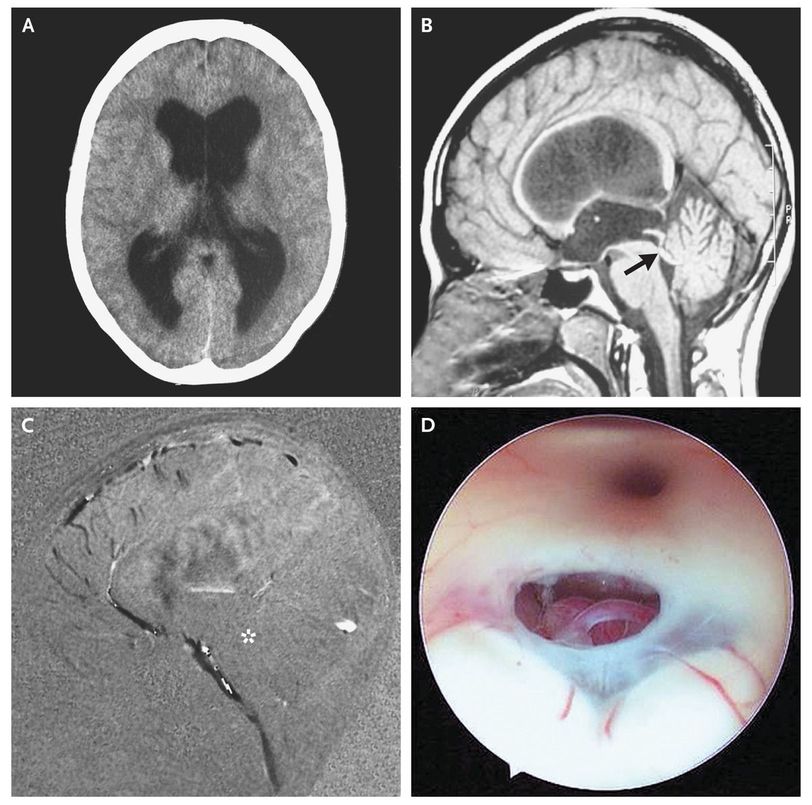

A 21-year-old woman presented with somnolence and confusion. She reported having progressively worsening headaches, nausea, and vomiting over the previous 5 months. Funduscopic examination showed bilateral papilledema as a clinical sign of intracranial hypertension. Computed tomography (Panel A) and magnetic resonance imaging (MRI) showed supratentorial hydrocephalus due to aqueductal stenosis (Panel B, arrow). Sagittal cine-phase MRI with the administration of contrast material showed a lack of flow-signal intensity at the aqueduct level (Panel C, asterisk). The patient received a diagnosis of idiopathic aqueductal stenosis, the most common form of obstructive hydrocephalus in adults. There was no evidence of a secondary cause of aqueductal stenosis, such as a tumor, infectious ventriculitis, or intraventricular hemorrhage. An endoscopic ventriculostomy was performed (Panel D) (seeΒ videos) by opening the floor of the third ventricle into the subarachnoid space of the brain-stem cisterns. This procedure treats idiopathic aqueductal stenosis by restoring the circulation of cerebrospinal fluid, without the need for an external ventriculostomy or ventriculoperitoneal shunt. There were no complications, such as meningitis, severe bleeding, new onset of neurologic deficits, leak of cerebrospinal fluid, or pneumocephalus. The patient had a good response to the procedure, with complete neurologic recovery. Five years later, she remained asymptomatic, and MRI showed no recurrence of hydrocephalus.